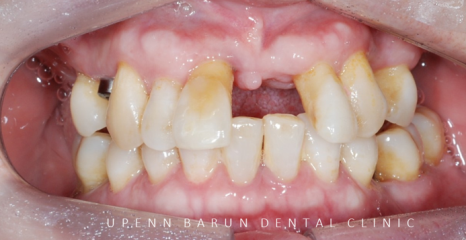

초진 정면사진

환자분께서는

현재 식사하기가 힘드신 상태로

윗니를 전체 임플란트를 하셔야 하는 상황인데다가

오른쪽 : 초진 파노라마

엑스레이와 함께 초진을 해보니

흔들리는 치아가 많이 있었으며

치주염으로 인해 치아들이 많이 정출되어 있었고,

어금니쪽에서 지지를 해 주지 못해

앞니끼리도 과도하게 맞물리고 있는 상태였습니다.